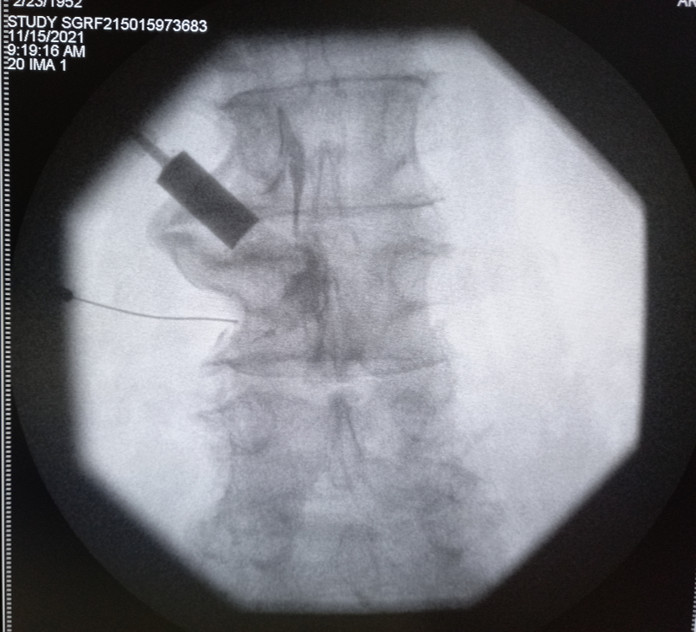

Hydrodilatation is a simple, minimally invasive treatment for frozen shoulder. It’s usually done in a clinic with a needle, although in more complex cases, it may be done in a special treatment room with X-ray guidance. The goal is to inject fluid into the shoulder joint to stretch the thickened joint capsule, help reduce inflammation and improve movement, and it can be done at any stage of the condition. This procedure is very effective. Most people see a big improvement in their shoulder's range of motion after just one injection. It not only helps with movement but also relieves pain, which is important because pain can make it harder to stretch the joint and improve mobility. Recovery is usually quick, and most patients can return to normal activities the same day. It's also recommended to do stretching exercises to help with recovery. Hydrodilatation is generally safe when done by experienced specialists, but it’s important to talk to your doctor about the benefits, risks, and other options before deciding if it’s right for you.